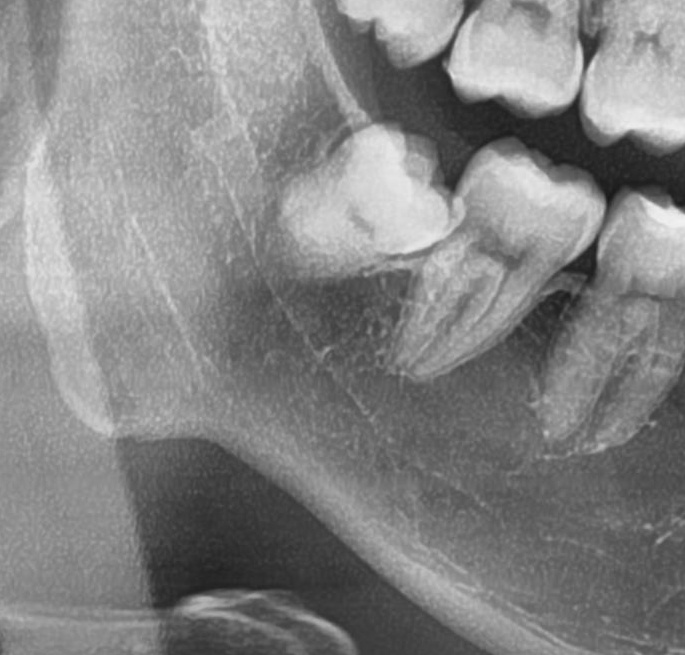

続いて2人目の患者様。

年末に右下の歯茎が腫れたとのこと。

確認してみると、右下の親知らずが歯茎の中でやや斜めに埋まっています。

抜歯開始。

抜歯終了。